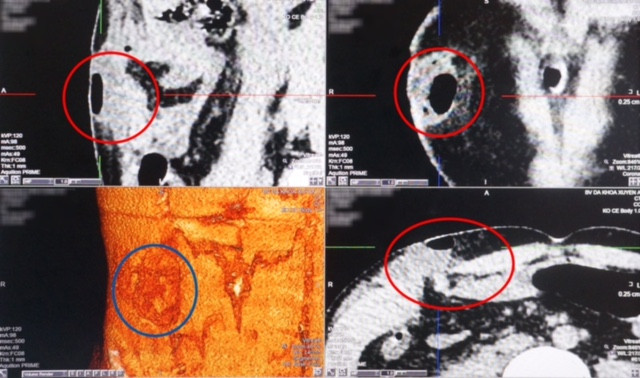

Hình ảnh chụp CT nạn nhân bị nhiều vết thương nguy hiểm.

TS-BS.Nguyễn Văn Châu, Tổng giám đốc bệnh viện đa khoa Xuyên Á cho biết, qua kết quả ảnh chụp CT 160 lát dựng 3D sọ não và bụng, bệnh nhân được xác định bị xuất huyết ngoài màng cứng vùng trán, gãy gò má 2 bên, vỡ sọ trán và hốc mắt phải. Không chỉ vậy, bệnh nhân còn bị vỡ thành bụng, thoát vị ruột dưới da, dập gan và xuất huyết trong bụng…